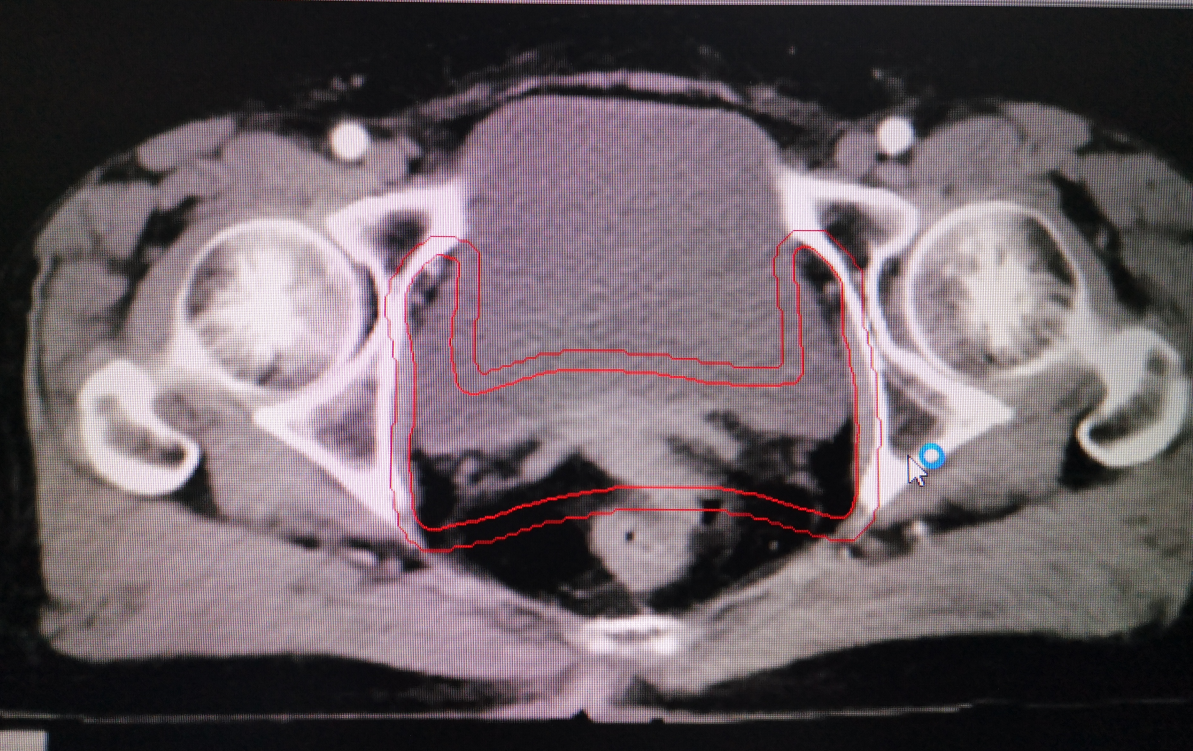

婦科腫瘤術後勾畫靶區示例:

其中,胃癌術後規範性預防性放(fàng)療為(wèi)我院首次開展。放(fàng)療前,嚴格按腫瘤放(fàng)療規範和靶區定義勾畫靶區範圍,放(fàng)療期間(jiān),在靶區照射野獲得足夠目标劑量同時(shí),危及器(qì)官受量均在劑量限制标準範圍之内,病人(rén)周圍器(qì)官損傷小,獲益大,實現(xiàn)了(le)真正意義的精準放(fàng)療。放(fàng)療後患者情況穩定,複查各項腫瘤指标均正常,影像學檢查未見異常,得到了(le)上(shàng)級醫(yī)院教授的肯定。